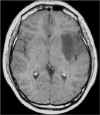

RM:

glioma con segni di trasformazione maligna